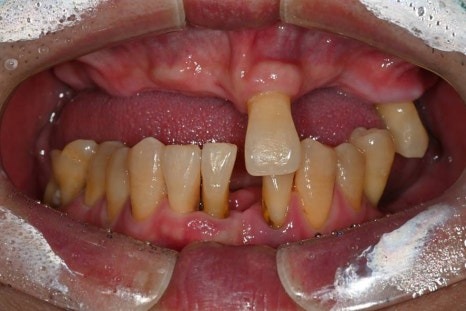

당뇨·고혈압을 모두 가지고 계셨던

전악 임플란트 케이스

이번에 소개해드릴 환자분은

당뇨와 고혈압, 두 가지 전신질환을

모두 가지고 계셨던 분으로

치아 결손이 광범위해

전악 임플란트가 필요한 상황이었습니다.

· 상악은 잇몸뼈가 매우 얇고 치아가 거의 남아 있지 않은 상태

· 하악은 부분 결손과 앞니의 심한 동요

· 식사가 어려울 정도로 기능 저하가 심한 상태

치료 전 / 치료 후

치료 전